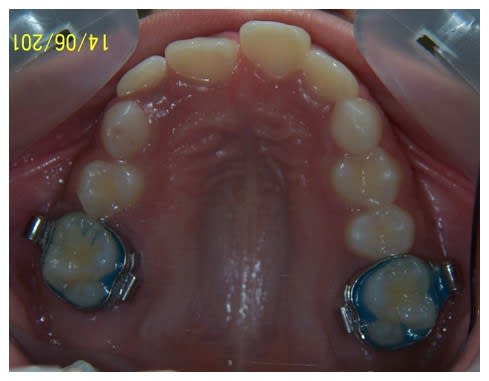

Je pense qu'il est tout à fait possible de trouver la place pour les prémolaires et cela vaut le coup de tenter avant d'extraire quoique ce soit.

Maintenant, on aimerait voir les faces occlusales des dents, et aussi un peu la forme du visage.. S'il y avait une télé, ce serait bien aussi.

Si les molaires sont effectivement en classe1, les incisives sont quand meme un peu en classe2 div2!!!! Elle a 10 ans, l'age ideal pour une FEO, apres, ils n'en veulent plus et ne les mettent pas, l'age ou l'on devient con arrivant vite! Et comme dit coluche, j'ai l'impression que chaque année, ils le deviennent de plus en plus en avance!

Dans cette phase d'interception, le Qhelix et la FEO me semblent pas mal.

Salut, amha il ne faut pas extraire. L'ortho veut certainement terminer en classe II thérapeutique mais à cet âge là, on a assez de croissance pour corriger le problème orthopédiquement. Je mettrai une plaque de hawley avec un verrin et une surélévation ant pour corriger la supra et permettre à la 23 de sortir. Et éventuellement enchaîner avec un appareil fonctionnel d'avancée mandibulaire…

Pour cette jeune fille , les cas d'agenesie d'incisive mandibulaire sont toujours durs a gerer pour moi et j'ai besoin d'une bonne observation clinique du patient ( exo, endobuccal) ,etude de moulages et radios ( tele pano ) pour decider de mon plan de traitement .